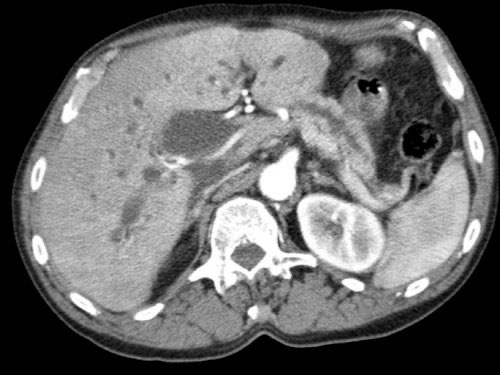

Tái tạo mặt phẳng coronal cho thấy:

- Bất thường bờ viền thành SMV được nhận thấy rõ hơn trên tái tạo coronal này (mũi tên).

- Khối u ở thân tụy (đầu mũi tên trắng).

- Huyết khối trong các nhánh bên của SMV (mũi tên xanh nhỏ).